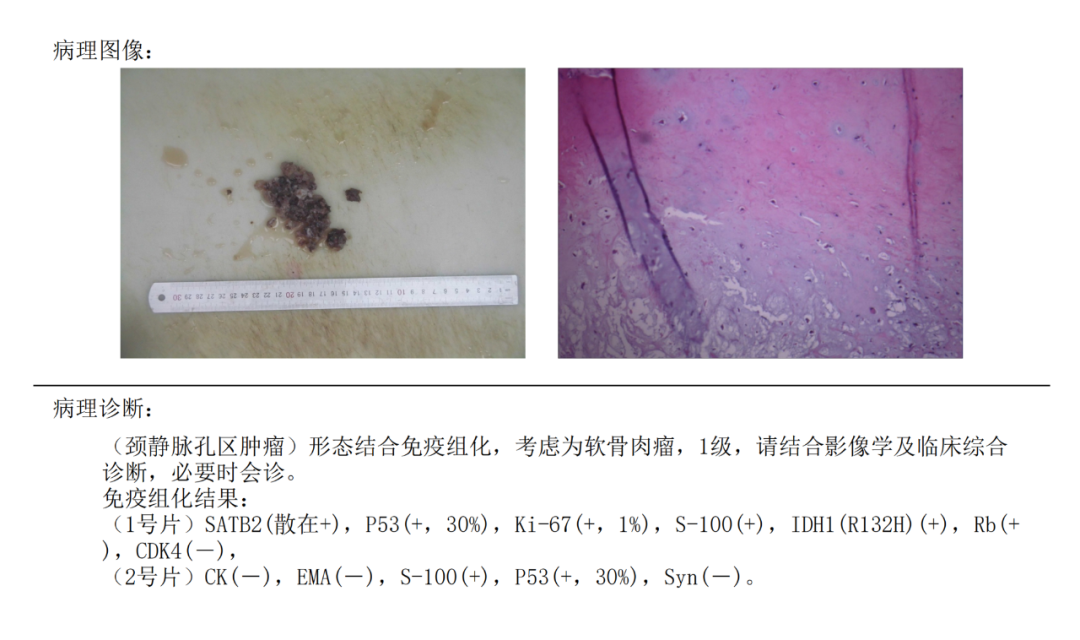

病例二

患者男性,56岁,左侧面瘫、声音嘶哑、饮水呛咳1年余。查体:神志清,口角右偏,左侧额纹变浅;左侧眼睑闭合不全,左侧鼻唇沟变浅,左耳听力下降,声音嘶哑,饮水呛咳,伸舌居中,颈软,无抵抗;四肢肌力、肌张力正常,腱反射正常,各生理反射存在,病理征未引出。

患者肿瘤较大,体表可触及,先于裸眼下切除颈部及枕下表浅肿瘤,之后在显微镜下根据需要磨除乳突骨质,充分暴露肿瘤后将其切除。